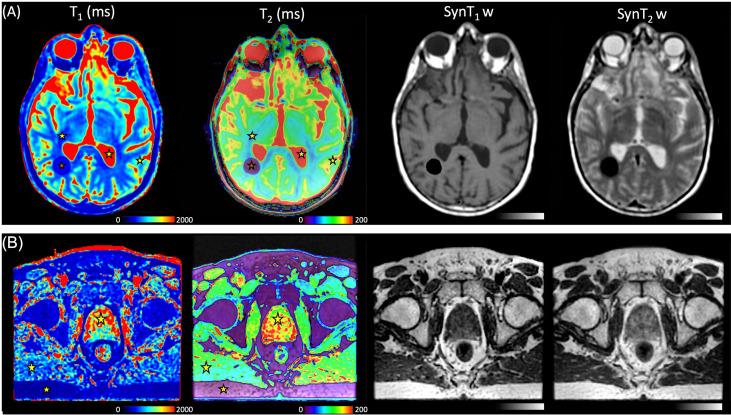

The phantom results showed good agreement (mean bias, 8.4%) between the two measurement methods for values between 490 and 2,385 ms and values between 25 and 400 ms. MAGiC gave discordant results for values below 220 ms (bias with the reference values, from 38% to 1,620%). measurements were accurately estimated below 400 ms (mean bias, 8.5%) by both methods. The QA assessments are in agreement with the recommendations of imaging for contouring purposes for radiotherapy planning. On patient data of the brain and prostate, the measurements of and by the two quantitative MRI (qMRI) methods were comparable (max difference, <7%).

体模结果显示,对于490至2385毫秒之间的 值和25至400毫秒之间的 值,两种测量方法之间具有良好的一致性(平均偏差为8.4%)。对于低于220毫秒的 值,MAGiC给出了不一致的结果(与参考值的偏差为38%至1620%)。两种方法在400毫秒以下均能准确估计 测量值(平均偏差为8.5%)。QA评估与放射治疗计划轮廓勾画成像的建议一致。在脑和前列腺的患者数据上,两种定量MRI(qMRI)方法对 和 的测量结果具有可比性(最大差异<7%)。